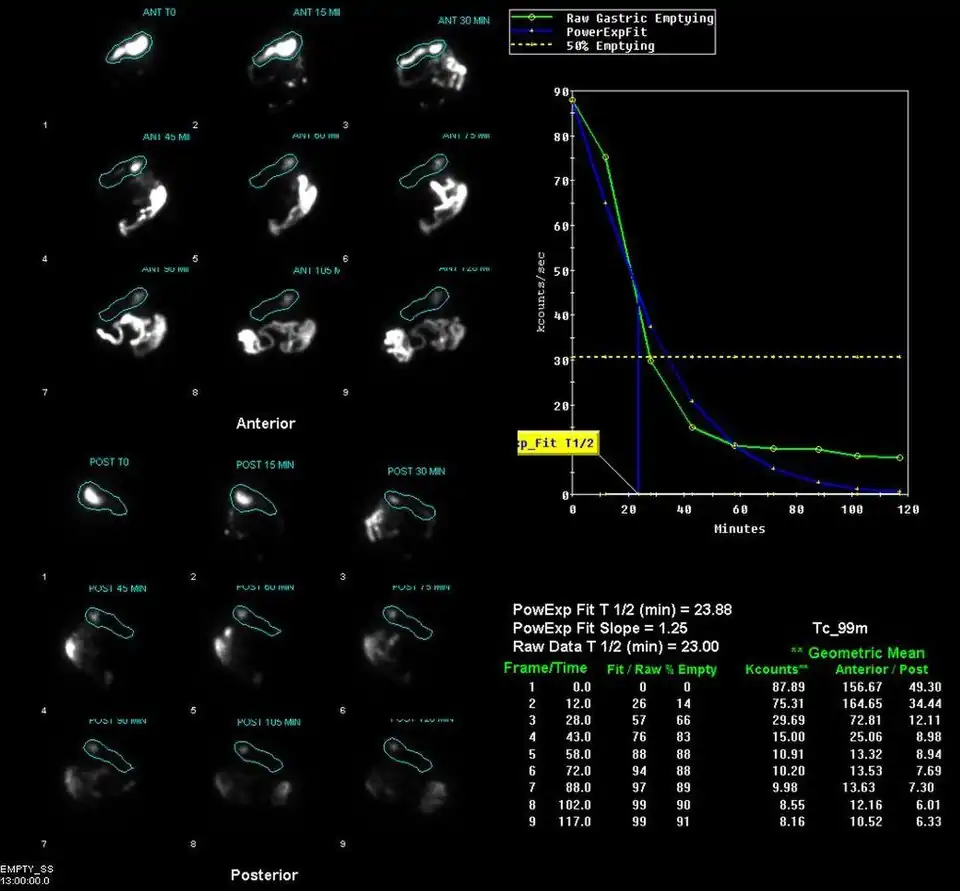

Example gastric emptying images | |

A gastric emptying study is a nuclear medicine study which provides an assessment of the stomach's ability to empty. It may be used if there are complications after gastric surgery, for gastric reflux, or suspected gastroparesis amongst other indications.[1] Scintigraphy that uses gamma cameras to create two-dimensional images is generally regarded as the gold standard for gastric emptying.[2][3]

The stomach time-activity curve is produced from geometric mean of anterior and posterior imaging. Half-emptying time, the lag-phase duration for solid studies, and percentage of food left at various time points are calculated.[7]